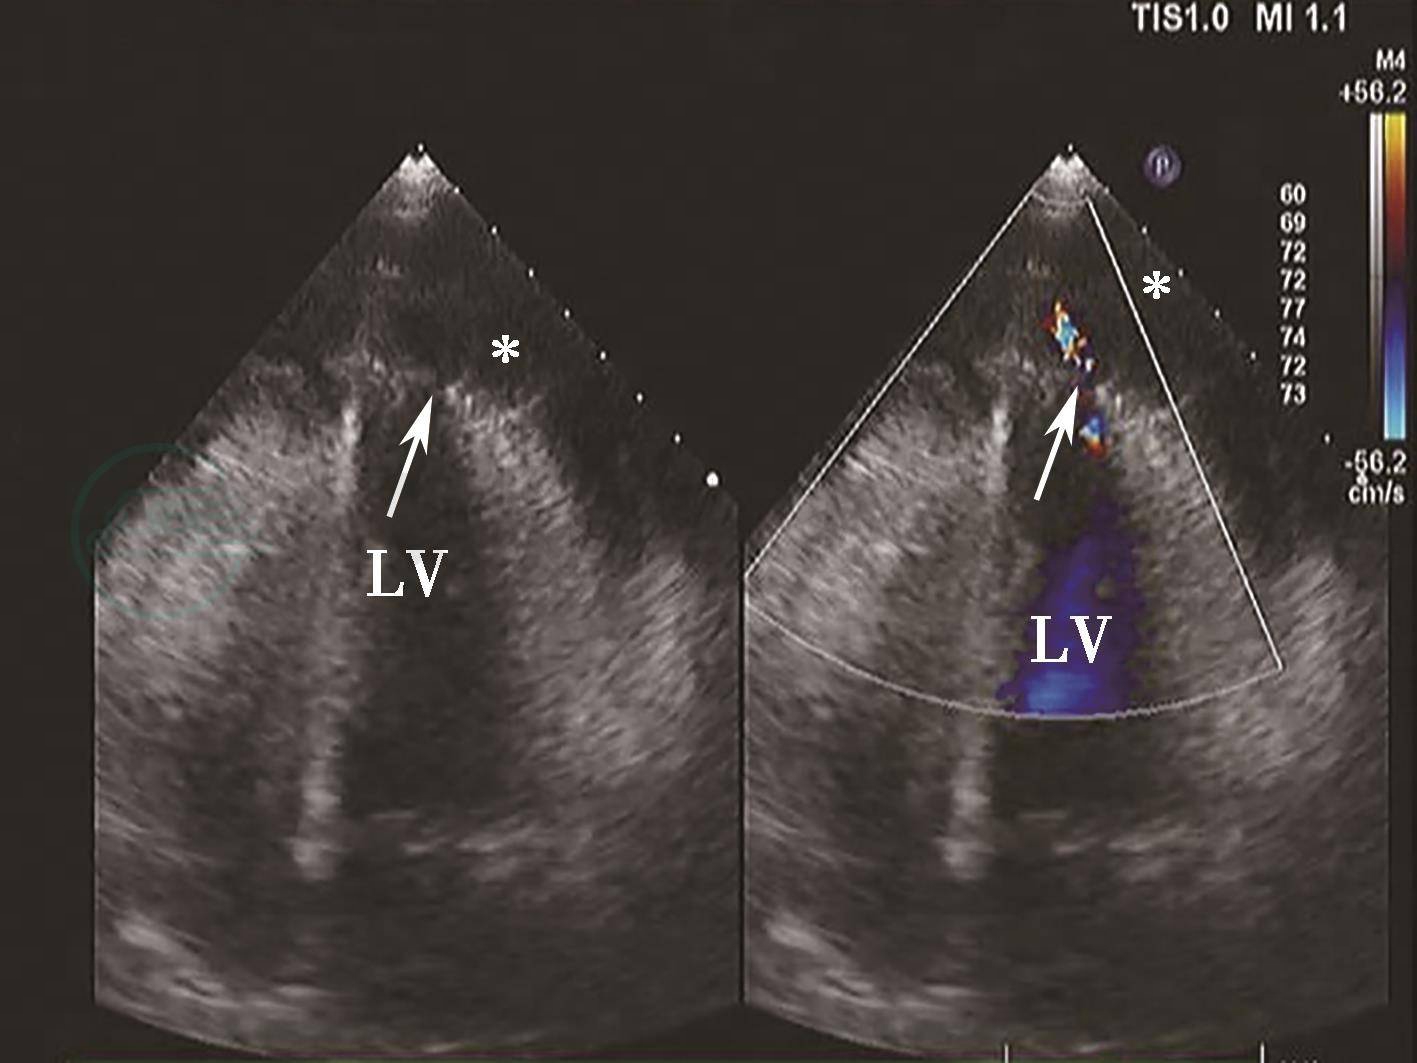

图1心肌梗死后左心室游离壁破裂二维切面图像及彩色多普勒血流图像

心尖四腔心切面(左图)显示左心室心尖部破裂(箭头示),彩色多普勒血流图像(右图)显示血流信号自该处进入心包腔(箭头示),心包腔内可见大量液性暗区(星号示)。LV.左心室。